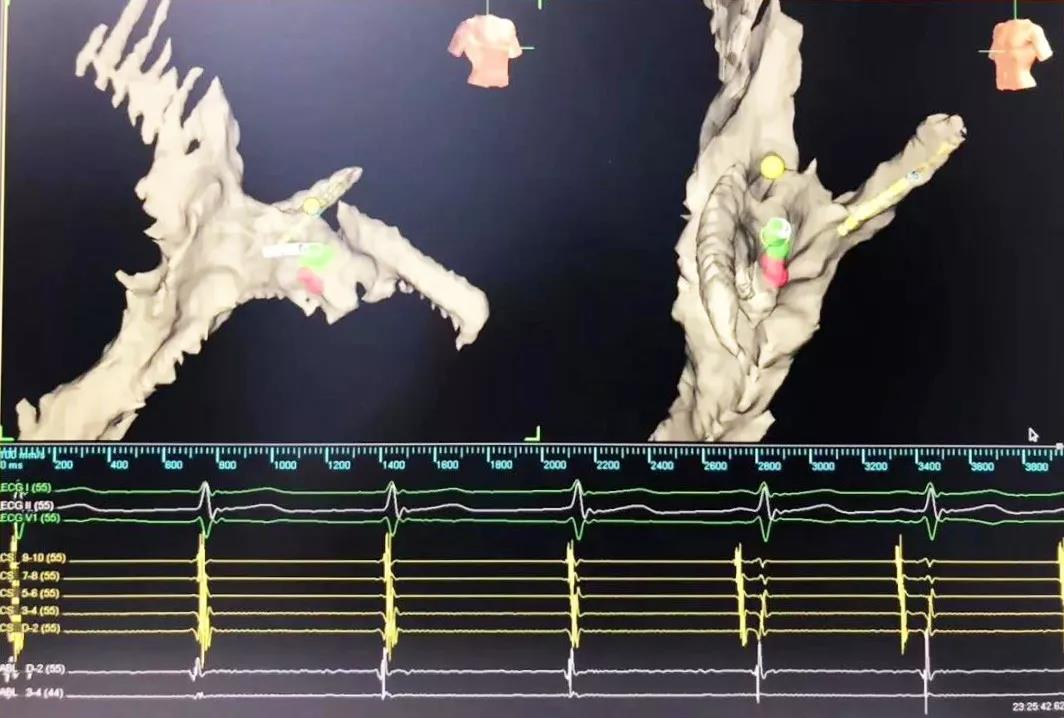

又一道難題擺在眼前,常規(guī)手術(shù)需要在X射線下進(jìn)行,X射線會(huì)導(dǎo)致胎兒發(fā)育畸形。在心臟病醫(yī)院院長(zhǎng)王海昌的帶領(lǐng)下,專家團(tuán)隊(duì)仔細(xì)研究后,決定為張女士施行三維標(biāo)測(cè)系統(tǒng)指引下零射線心臟電生理檢查及射頻消融術(shù)。

在完成常規(guī)檢查,排除新型冠狀病毒肺炎的可能后,217日,由廉誠主刀,在三維標(biāo)測(cè)系統(tǒng)指引下行零射線心臟電生理檢查及射頻消融術(shù)。術(shù)中明確患者心動(dòng)過速為房室結(jié)折返性心動(dòng)過速,遂行房室結(jié)慢徑改良,消融完畢后反復(fù)刺激驗(yàn)證,心動(dòng)過速均不能誘發(fā),手術(shù)成功,歷時(shí)約1小時(shí),全程零射線完成。這也是西安國際醫(yī)學(xué)中心醫(yī)院心臟病醫(yī)院的首例零射線治療特殊人群心律失常病例。